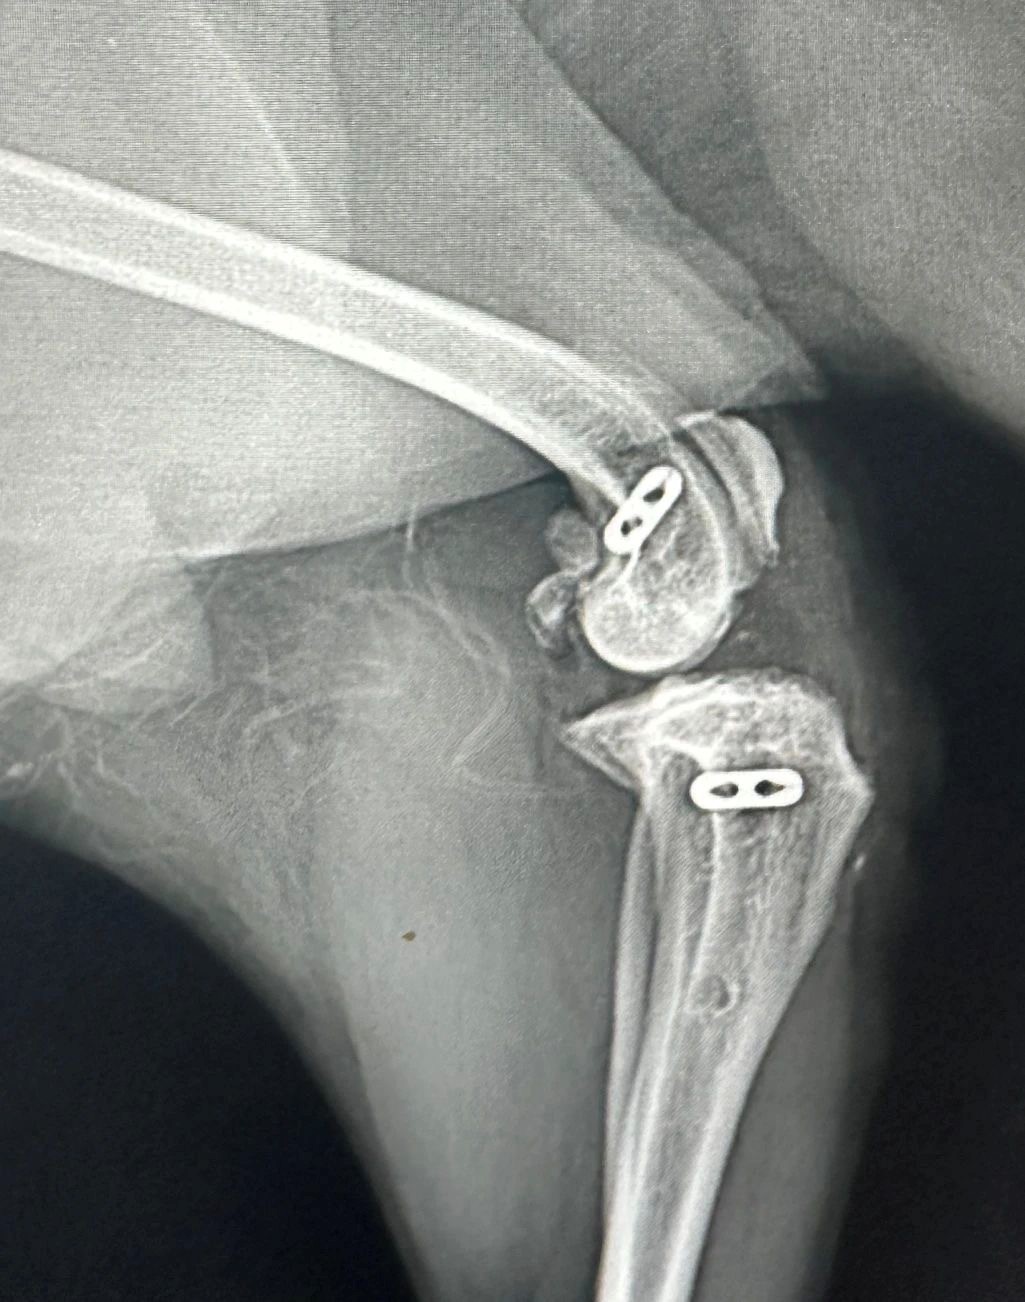

Figures 4 & 5. Post-op X-rays